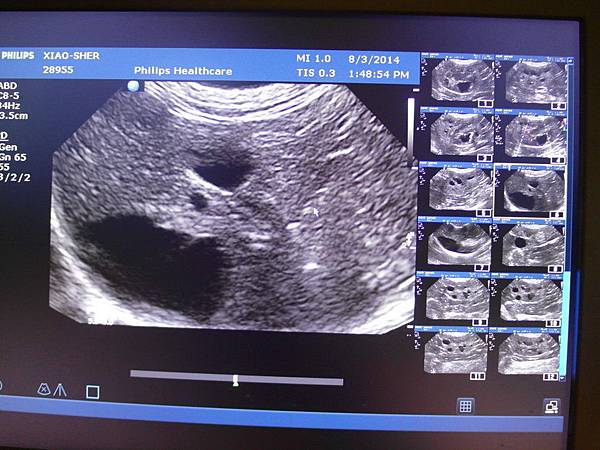

超音波的部分

發現了囊肝

上次超音波沒發現,但其實真正的膽囊被囊肝壓在後面,

因為角度的關係所以沒看到

下面黑黑的是囊泡,後面黑的是膽囊

膽囊的型態還正常,沒有膽泥淤積或擴張

腎臟型態跟之前差不多,血液灌流都還ok

左腎的有一個比較大的囊約1cm,較小的約0.5cm約有4個

右腎有0.4~0.6cm的囊約5個

肝臟在膽囊尾側的囊約2*1.2cm